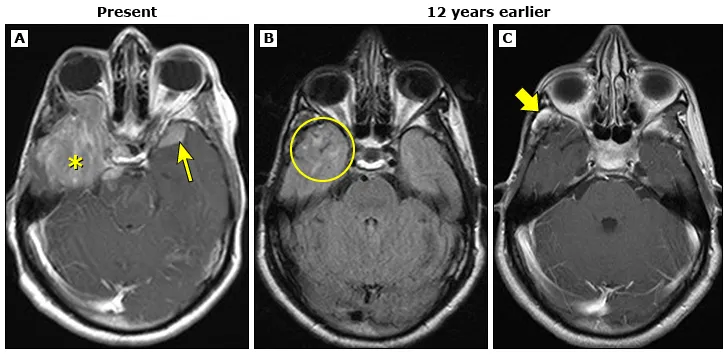

10岁时,她为战胜横纹肌肉瘤,接受了高剂量放疗。殊不知,这救命的治疗,却在脑中埋下隐患。12年前的影像(图B-C)已初现端倪,右颞叶放疗后白质损伤(圆圈)及原肿瘤区增生肉芽组织(粗箭头)。

如今,一个巨大的脑膜瘤(图A)浮出水面,巨大轴外强化肿块(*),侵及右侧眶内、鞍区及桥前池;左侧蝶骨大翼另见一较小硬膜基底病灶(箭头)。右颞病灶病理证实为脑膜瘤。这并不是偶然,而是二十七年前治疗带来的结果。